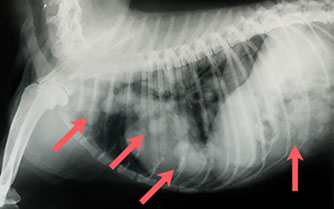

Zwei Diabologeschosse im Körper einer Katze